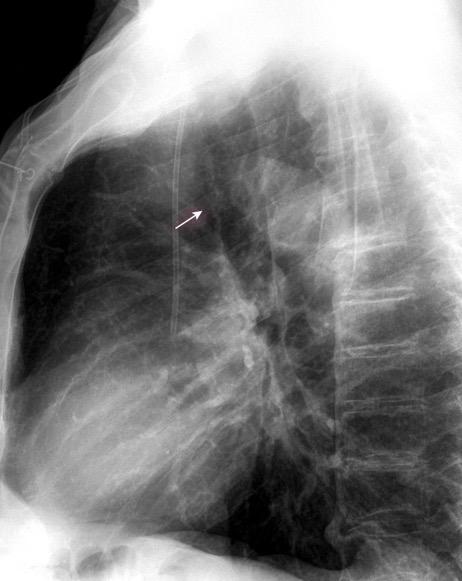

Mounier-Kuhn

Traqueobroncomegalia de Mounier-Kuhn con neumonía del LID

Traqueobroncomegalia de Mounier-Kuhn

Dilatación marcada de tráquea y grandes bronquios.

Traqueobroncomalacia 67% + Protrusión del tejido músculo-membranoso redundante entre los anillos cartilaginosos.(diverticulosis traqueal)

Infección respiratoria recurrente (88%)

Debilidad del aparato muco -ciliar Fumadores.